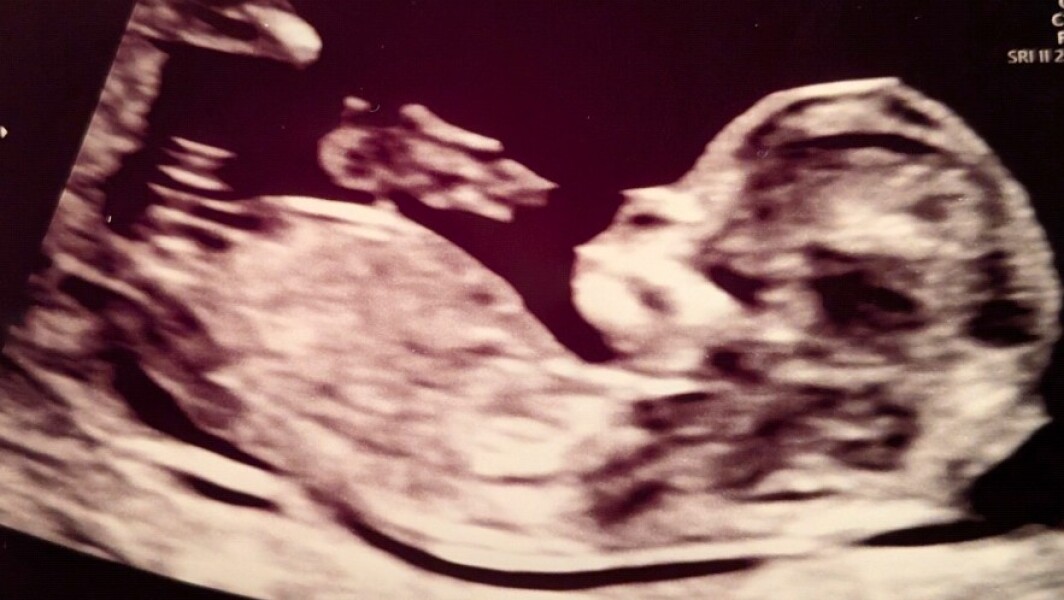

Hey would anyone be able to tell mine , I don’t have a clue what I’m looking at 12 weeks and 6 days

Looks like a girl to me too. Xx

Awww thank you ahhhhh another girl I was really preying for a boy I fee awfuL Saying that xx